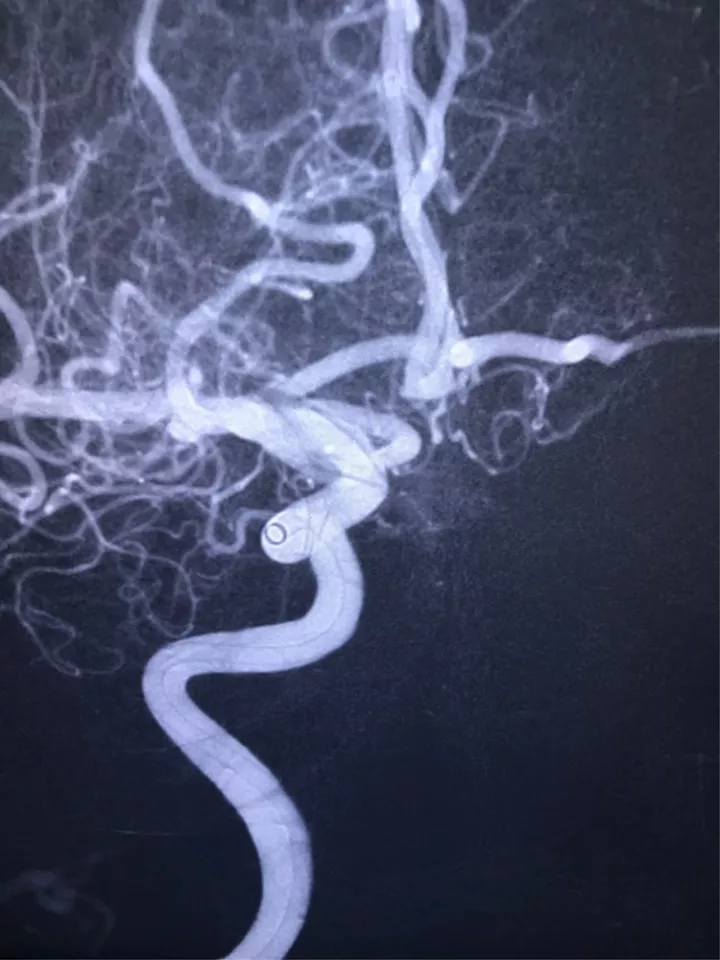

找到支架与弹簧圈之间的切线位,继续填塞。支架很好地保护住了颈内动脉和后交通动脉

最后的填塞结果